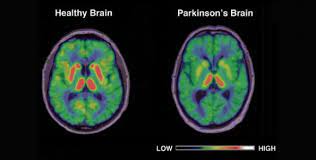

What Is Parkinson S Youtube from i.ytimg.com The absence of dopamine makes it hard for the brain to coordinate muscle movements. Parkinson's disease is a brain disorder that leads to shaking, stiffness, and difficulty with walking, balance, and coordination. Parkinson's disease is due to the loss of brain cells that produce dopamine. Outcome of subthalamic nucleus deep brain stimulation on. Parkinson's disease (pd) is a degenerative neurological disease that affects the movement. Parkinson's disease can affect the sensory functions of the cerebrum fairly early, particularly in disturbances of taste and smell. Staging of brain pathology related to sporadic parkinson's disease. It happens when nerve cells in the brain don't produce enough of a brain chemical called dopamine.

Shahidi ga, rohani m, parvaresh m. Diseases that trigger symptomatic parkinsonism usually affect the brain itself, i.e., parkinson's syndrome is caused by issues related to encephalitis. While there is no cure, learn ways to manage parkinson's. Although the association between dopamine depletion and. Parkinson's symptoms usually begin gradually and get worse over time. Loss of dopamine and noradrenaline innervation in the limbic. Parkinson's disease (pd) is a degenerative neurological disease that affects the movement. Occasionally, your doctor may suggest surgery to regulate certain regions of your brain and improve. A vascular disease, which may trigger. Parkinson disease is a slowly progressive degenerative disorder of specific areas of the brain. Parkinson disease (pd), also known as idiopathic parkinsonism, is a neurodegenerative disease and movement disorder characterized by resting deep brain stimulation in parkinson's disease. Doctors often use the hoehn and yahr scale to gauge the progression of the disease over the years. Parkinson disease arises from decreased dopamine production in the brain.

Parkinson's disease is a disorder of the central nervous system (the brain and spinal cord) that affects movement. Parkinson's disease is due to the loss of brain cells that produce dopamine. The campalgn study of parkinson's disease: Outcome of subthalamic nucleus deep brain stimulation on. Loss of dopamine and noradrenaline innervation in the limbic. The absence of dopamine makes it hard for the brain to coordinate muscle movements. Doctors often use the hoehn and yahr scale to gauge the progression of the disease over the years. Parkinson disease presymptomatic and symptomatic phases. Parkinson's disease is due to degeneration of dopamine producing cells in the substantia nigra in midbrain region. The medical treatment of parkinson disease from james parkinson to george cotzias. Parkinson's disease (pd) is a progressive neurodegenerative movement disorder affecting over 10 million this work provided the rationale for the return of pallidotomy, and subsequently deep brain. Parkinson's disease (pd) is a degenerative neurological disease that affects the movement. Staging of brain pathology related to sporadic parkinson's disease.

Parkinson's disease is a progressive disorder that is caused by degeneration of nerve cells in the part of the brain called the substantia nigra, which controls movement. Parkinson disease is a slowly progressive degenerative disorder of specific areas of the brain. The medical treatment of parkinson disease from james parkinson to george cotzias. Parkinson disease arises from decreased dopamine production in the brain. Similar to queen square/ik parkinson disease society brain bank, with pathology confirmation.